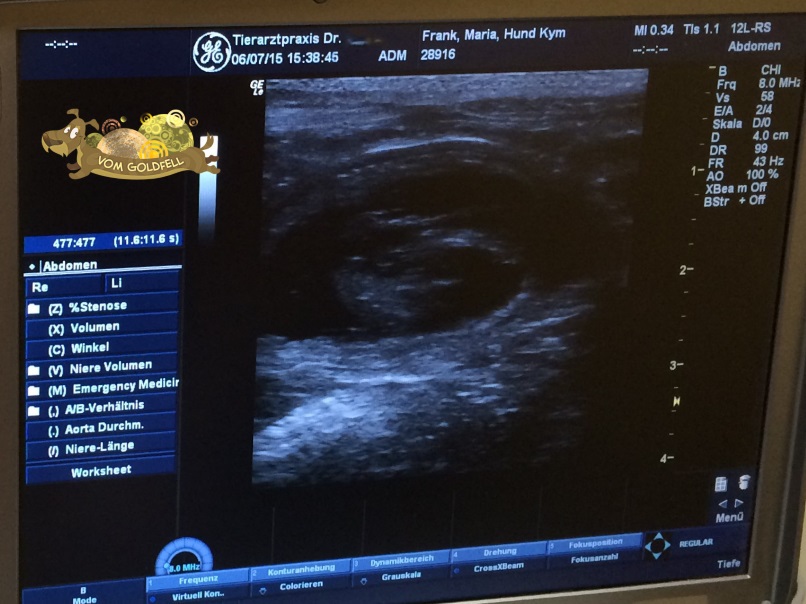

Ultraschall von Kym am 06.07.2015

Update per 06.07.2015:

Hurra - es hat wieder geklappt: Auch Kym ist trächtig!

Wir waren heute mit Kym zur Ultraschalluntersuchung.

Dabei wurden auch bei Kym zwei Welpen deutlich gesichtet.